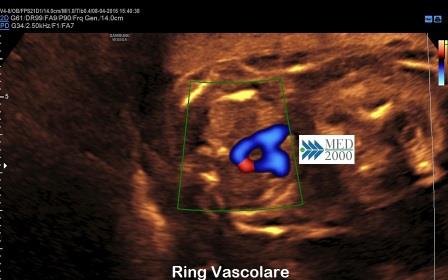

E' una variante associata nel 10% dei casi ad altre cardiopatie congenite ed è più frequentemente sintomatica (anche tardivamente dopo la nascita) poichè i vasi anomali presenti (ring vascolari) possono causare effetti compressivi sulla trachea o sull'esofago (disfagia lusoria).

- nella scansione dell'arco aortico (scansione trasversale più alta) si osserva una "U" dove: la branca sinistra è rappresentata dall'arteria polmonare, la branca destra è rappresentata dall'arco aortico che si trova a destra della trachea; la trachea si reperta nella parte interna della U. La congiunzione delle due branche della U è un vaso anomalo rappresentato dall'arteria succlavia sinistra aberrante che, decorrendo dietro la trachea e l'esofago, va a formare un ring vascolare retrotracheale.

La diagnosi ecografica si pone per la presenza di ring vascolari